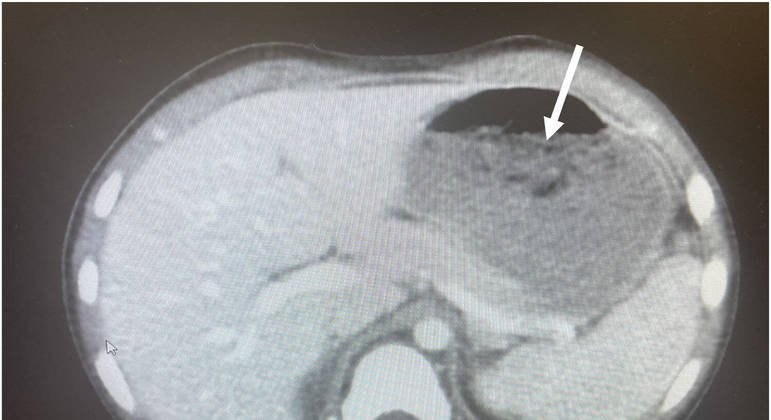

Foi realizada inicialmente uma TC (tomografia computadorizada) de abdômen e pelve que “mostrou distensão gástrica com líquido e detritos”, sendo difícil que os médicos determinassem o que poderia ser uma refeição — ele havia tomado café da manhã — ou o bezoar.

Os profissionais procederam então com um exame de esofagogodenoscopia diagnóstica e terapêutica, que revelou um bolo de goma de mascar que preenchia aproximadamente 25% do estômago do paciente.